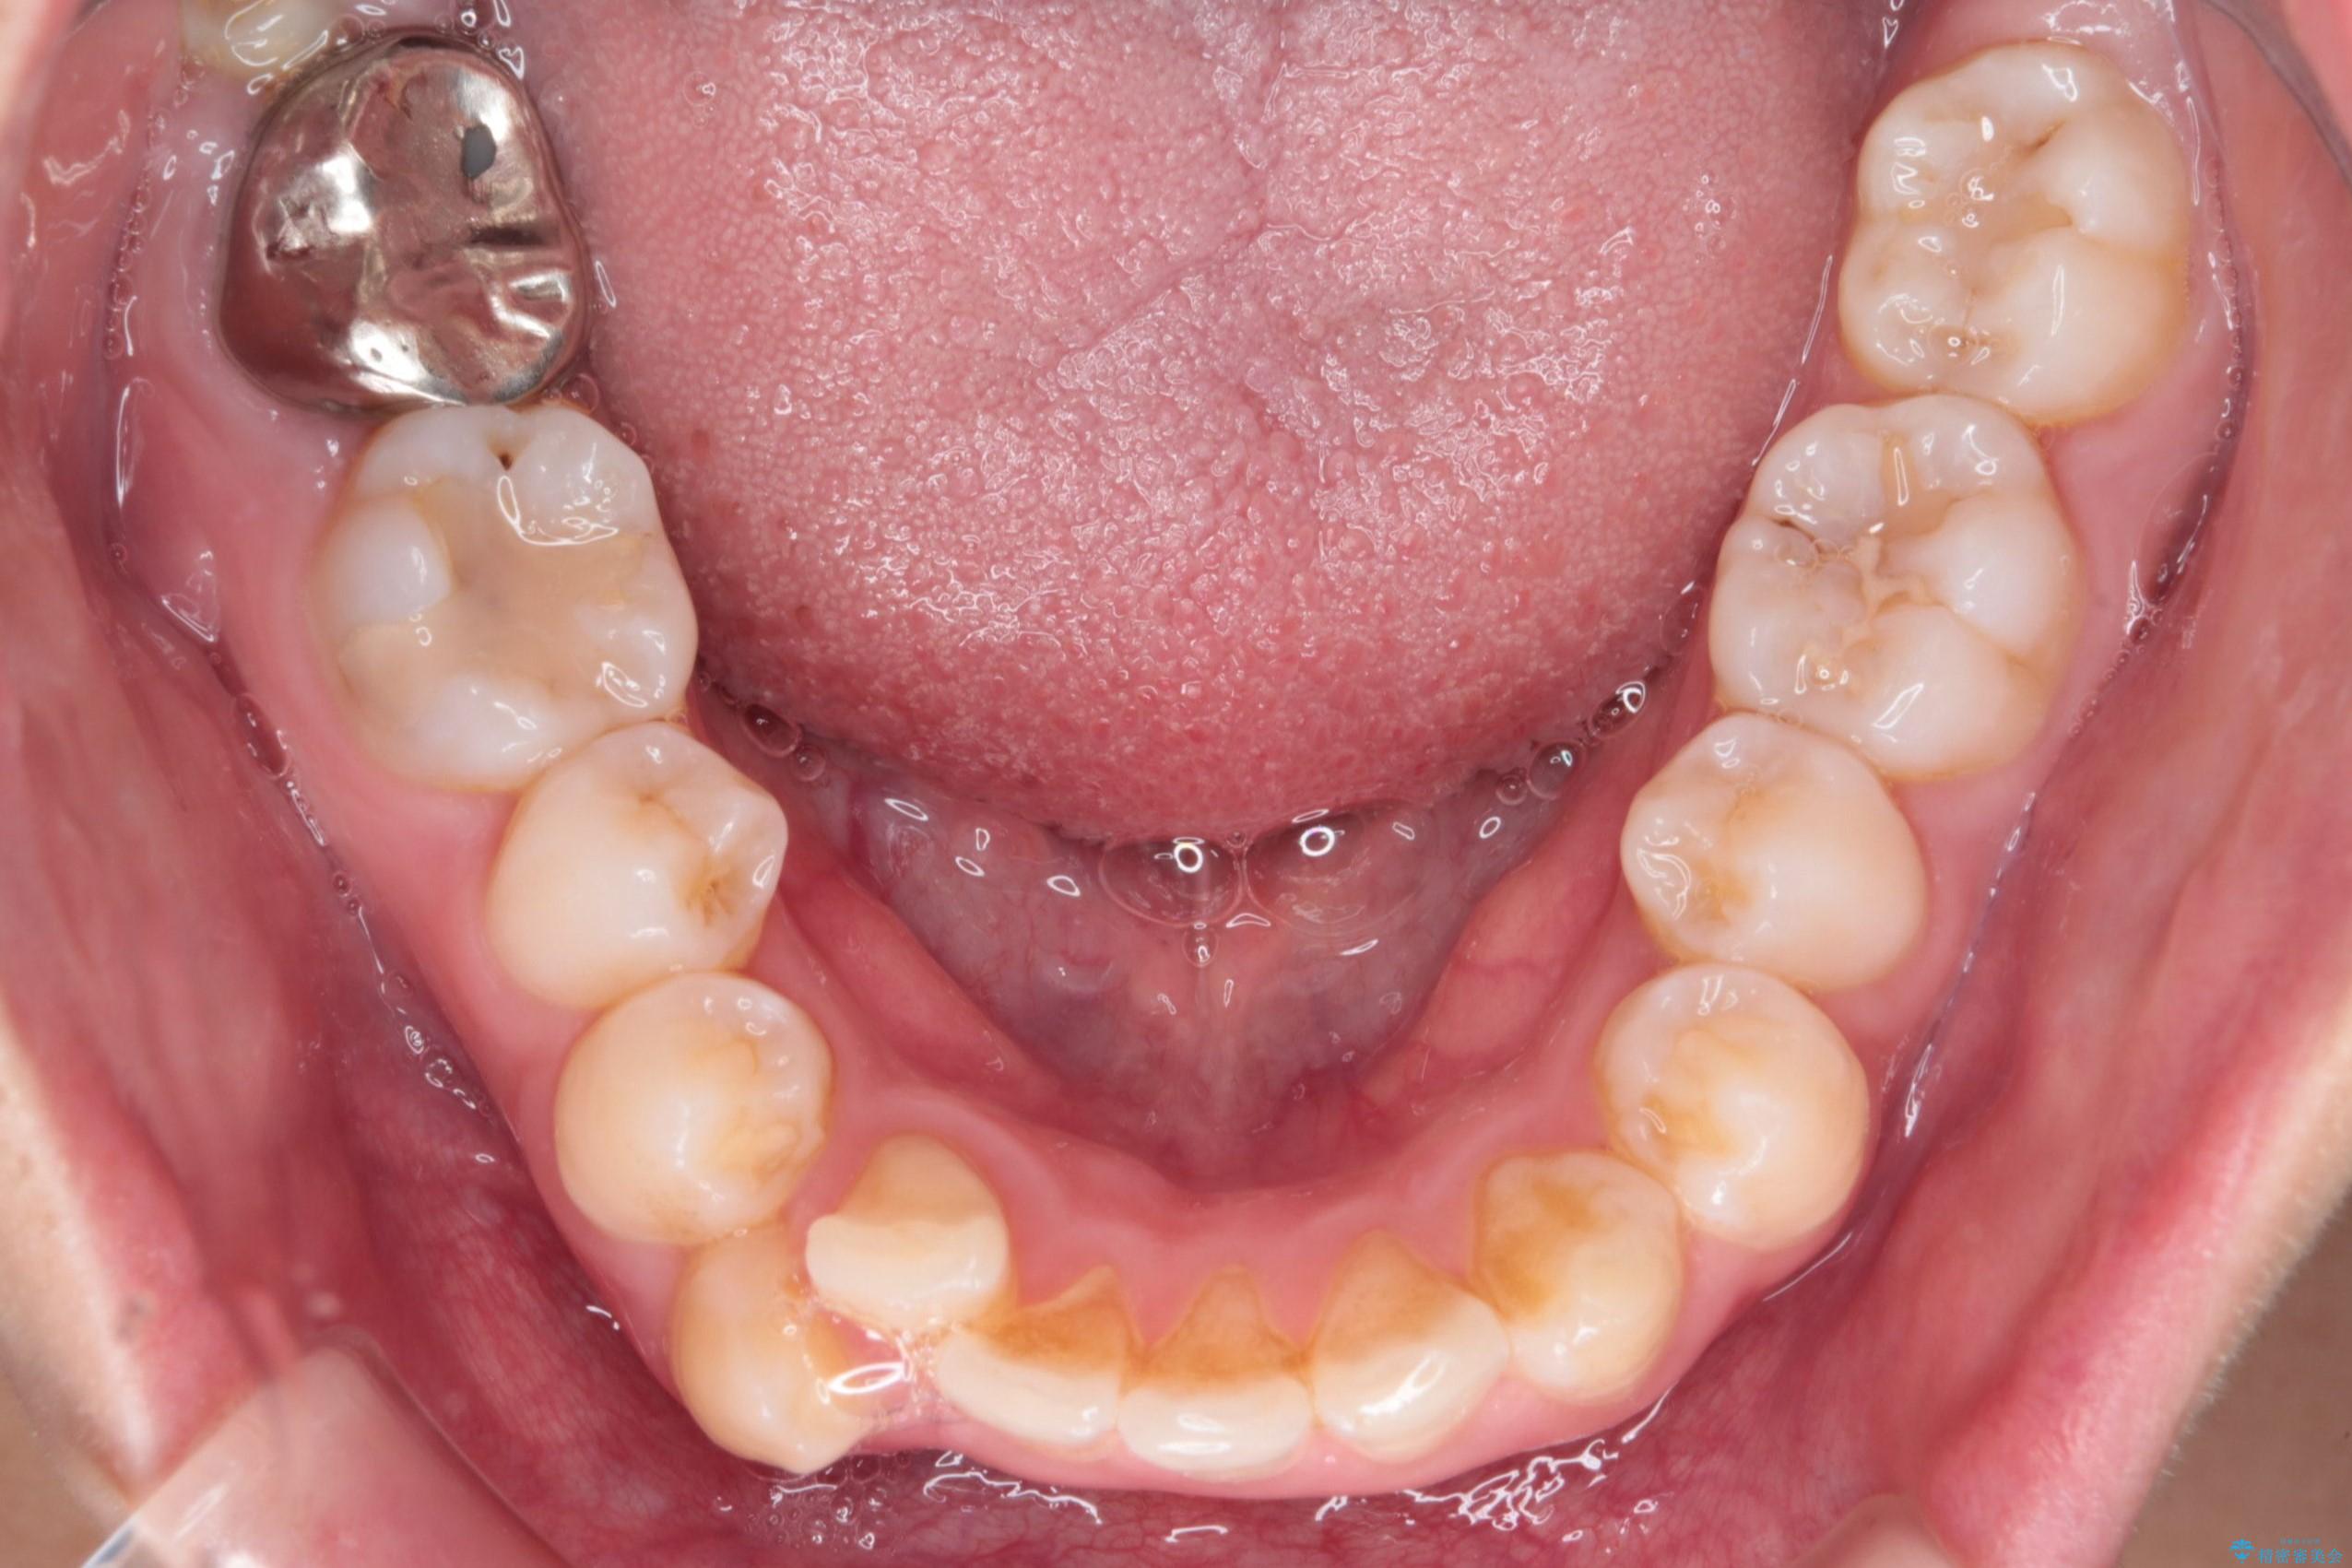

- 前歯から奥歯にかけて歯の重なりが激しい歯のがたつき(重度叢生)を主訴にご来院されました。精密検査の結果、歯が並ぶスペースが大幅に不足しており、歯並びを整え、口元を美しく引っ込めるためには、スペースの確保が必要と診断しました。そこで、上下左右の第一小臼歯(4番目の歯)を計4本抜歯し、そのスペースを利用して歯並び全体を整える抜歯矯正の治療計画を立案。装置には、透明で目立たないインビザラインを採用し、審美性と治療効果の両立を目指しました。

今回の治療では、重度の叢生を改善するため、まず計画通り上下左右4本の小臼歯を抜歯し、歯を並べるための十分なスペースを確保しました。装置には透明で取り外し可能なインビザラインを使用。抜歯によってできたスペースを最大限に活用し、マウスピースを定期的に交換しながら、デコボコを解消しつつ、前歯を効果的に後退させました。

治療の結果、長年の悩みであった重度の歯のがたつきが解消され、口元の突出感も改善。機能的にも安定し、審美的にも美しい、理想的な歯並びを獲得していただけました。